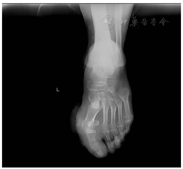

患者男,53岁,因"左足皮肤红肿、流脓、破溃1周余"于2018年11月2日入住我院烧伤科。患者1周前发现左足拇指破溃,流脓,自行外用碘伏换药,口服抗菌药物(具体不详)治疗,效果不佳,后左足拇指及足底、足背红肿明显,多处破溃,伴有疼痛、流脓加重,遂来我院就诊。患者精神尚可,体力正常,食欲、睡眠正常,体质量无明显变化,二便正常,偶有咳嗽、咳痰,无胸闷、气短。平素健康,否认糖尿病、冠心病等疾病史。2017年10月当地医院确诊高血压病,口服降压药物,具体不详,血压未予正规监测。否认肝炎、结核、疟疾等传染病史,否认手术史、外伤史、输血史、药物、食物过敏史,预防接种在当地进行。入院检查:体温40.0 ℃,脉搏68次/min,呼吸18次/min,血压121/75 mmHg(1 mmHg=0.133 kPa)。发育正常,营养良好,面色红润,自动体位,步入病房,步态蹒跚,神志清楚,语言正常,声音洪亮,对答切题,查体合作。除病变皮肤外其他皮肤颜色正常,无黄染、皮疹及皮下出血,全身浅表淋巴结未触及肿大。心脏相对浊音界正常,心率157次/min,律齐,各瓣膜听诊区未闻及杂音。专科情况:左足拇指、足背及足底红肿明显,多处溃疡创面,流脓明显,疼痛明显。实验室检查:白细胞计数(WBC)11.5×109/L,中性粒细胞占0.911,红细胞(RBC)3.19×1012/L,血红蛋白(Hb)114 g/L,血小板(PLT)670×109/L,全血C-反应蛋白(CRP)172.20 mg/L,血清白蛋白(Alb)27.3 g/L,血清Na+ 132.7 mmol/L,血清Cl- 95.2 mmol/L,活化部分凝血活酶时间46.0 s,D-二聚体2.95 mg/L。影像学检查:胸部CT平扫未见异常;心脏彩超:主动脉硬化改变,三尖瓣返流(轻度);左足X光检查如图1所示:左足拇趾外翻,第一趾周围软组织肿胀,密度欠均匀。初步诊断:左足皮肤破溃伴感染,高血压病,窦性心动过速,菌血症。予清创、口服布洛芬混悬液降温、口服硝苯地平缓释片(30 mg/d)和酒石酸美托洛尔(25 mg,2次/d)降血压,予创面分泌物细菌培养+药敏试验,予血液细菌培养+药敏试验。11月2日送检血培养一套(需氧+厌氧),11月3日血培养一级报告:厌氧瓶生长革兰阳性球菌,报阳时长27.5 h(需氧瓶5 d未见细菌生长),显微镜下菌落形态如图2所示。11月4日分泌物细菌培养:金黄色葡萄球菌。药敏试验结果:头孢西丁筛选阴性,苯唑西林、环丙沙星、万古霉素、利奈唑胺敏感,青霉素、红霉素、克林霉素耐药。临床应用左氧氟沙星注射液(0.5 g,1次/d)+头孢唑啉钠注射液(2 g,1次/8 h)抗感染治疗,重复送检一套血培养未生长细菌。11月5日,患者体温又升高至39.2 ℃,血培养二级报告MALDI-TOF MS鉴定:黑尔嗜胨菌(Bruker microflex LT MALDI-TOF MS最高得分2.118,同时送16S rRNA测序,测序结果不解糖嗜胨菌总分2470,黑尔嗜胨菌总分2453)、大芬戈尔德菌(MALDI-TOF MS最高得分1.971,Vitek Compact 2 ANC鉴定大芬戈尔德菌99%概率)。根据血细菌培养结果,调整抗菌药物为甲硝唑氯化钠注射液(0.5 g,1次/12 h)+哌拉西林/他唑巴坦钠注射液(4.5 g/8 h)。11月7日行左足感染性皮肤扩创负压封闭引流术。11月8日查体,体温36.2℃,脉搏88次/min,术后第二天饮食睡眠如常,二便正常,自诉无明显不适,无发热。11月10日复查WBC 8.7×109/L,中性粒细胞0.587,RBC 3.13×1012/L,Hb 110 g/L,PLT 811×109/L,血清Alb 28.1 g/L,D-二聚体0.79 mg/L,复查显示仍为低蛋白血症,嘱增加营养,感染明显改善。11月13日停止甲硝唑氯化钠注射液治疗,哌拉西林/他唑巴坦继续用至第14天。11月15日行左足植皮术,11月22日患者出院,2个月后回访,患者恢复良好,已正常工作生活。